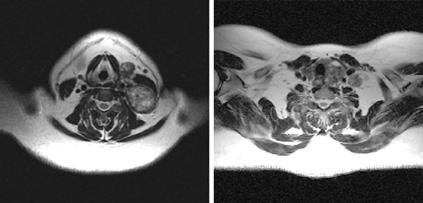

Исследования, проведенные нами в последние годы у 65 больных раком щитовидной железы, показали, что применение РКТ в сочетании с МРТ позволяет в высоком проценте случаев до операции иметь информацию о взаимоотношении распространенной опухоли щитовидной железы с окружающими анатомическими структурами (рис. 3, 4, 5).

Рисунок 5. МРТ: опухолевое поражение нижнего полюса левой доли щитовидной железы